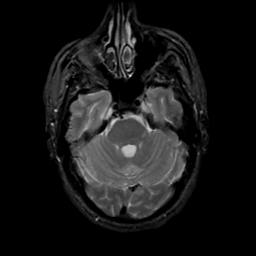

MR Study #8, March 31, 1991 -- Slice #14

[Home][Help][Clinical][Tour 1][Tour 2] Slice 14